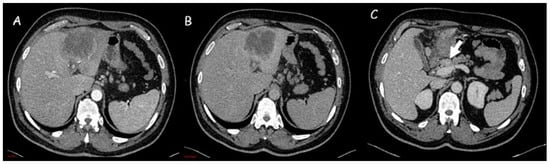

Figure 2.

(A,B) Computed tomography imaging of an intrahepatic cholangiocarcinoma of approximately 8 cm in the left hepatic lobe, with capsular retraction, central hypodensity, and inhomogeneous enhancement due to necrotic-colliquative phenomena. Peripheral rim enhancement in the arterial phase (A) with progressive contrast filling in the subsequent phases (B). (C) Locoregional lymph nodes (white arrow).